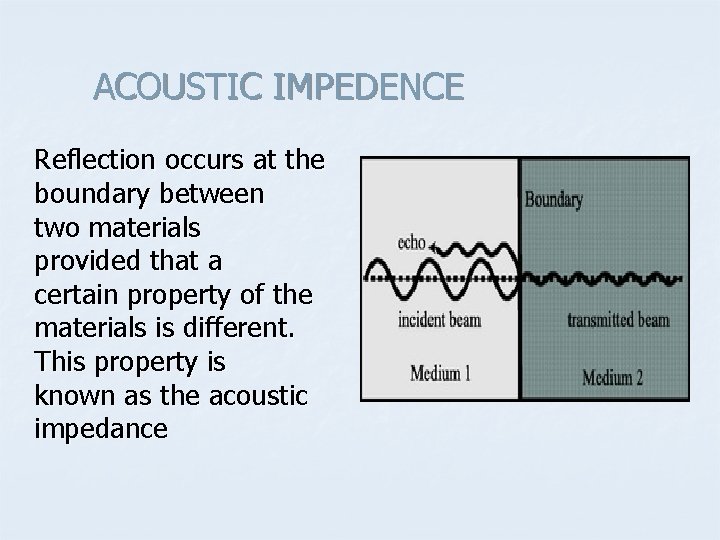

ACOUSTIC IMPEDENCE Reflection occurs at the boundary between two materials provided that a certain property of the materials is different. This property is known as the acoustic impedance